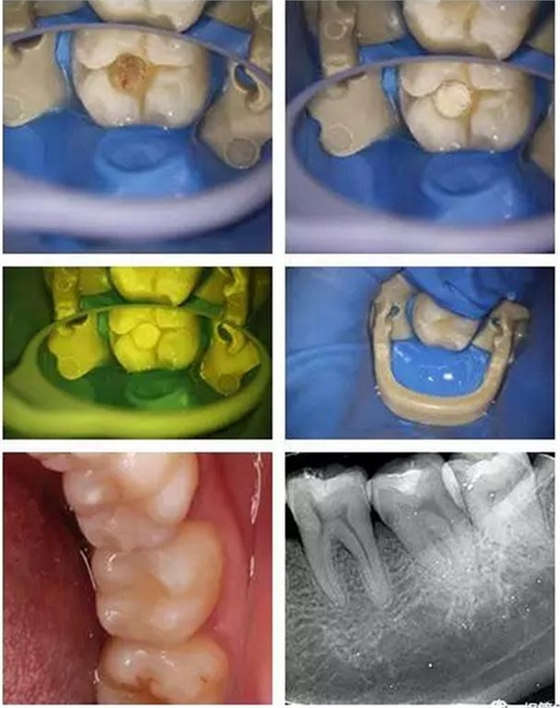

接下來(lái)給大家分享一個(gè)喻剛醫(yī)生的顯微鏡下直接美學(xué)樹(shù)脂修復(fù)后牙深齲的病例,讓大家更加清楚的了解深齲的治療!

顯微鏡下非常精確與清晰的去凈齲壞組織,精細(xì)的操作盡最大程度保留剩余健康牙本質(zhì),這也需要醫(yī)生精湛的技術(shù)!

美學(xué)樹(shù)脂分層堆塑,還原本真!